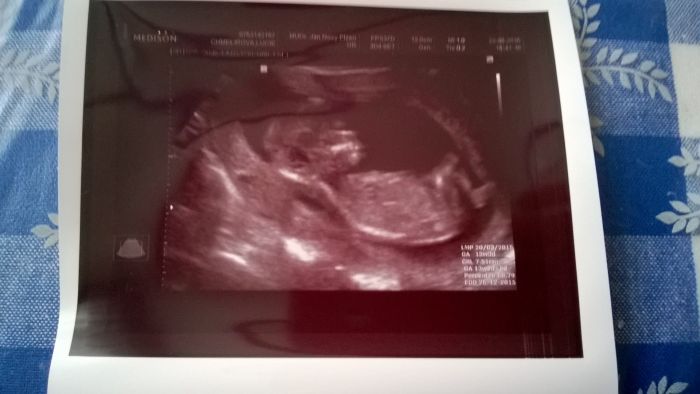

Bety,na plodovku bych nemusela jít,kdybych řekla,že nechci...je to jen na doporučrní,prvně mě to doporučil můj gynekolog a dnes mě objednával na ten screening který dělají na genetice v Plzni,a paní na druhé staně něco říkala doktoru a on na to: paní má 36let ale v době porodu jí bude 37 let...a pak jen řekl,pacientka je s tím seznámená a na odběr půjde...takže asi tak :-) Samozdřejmně že pokud by byl nějaký problém,tak na plodovku chodí i mladší maminky a hlavně ne dobrovolně ale na žádanku...ale já pro klid v duši a hlavně pro jistotu,že ten brouček bude v pořádkuprostě bez váhání jdu :-) Jinak děvčata,dnes mi dělal dr takový podrobnější utz,a po 10 minutách mi řekl,že první odhad na 60% je chlapeček :-) Ale nemám to brát vážně a na 100% :-) Tak jsem zvědavá,páč opět mám stejný pocit jako u syna...že čekám chlapečka :-) A jak jsem slíbila přikládám fotečky :-)